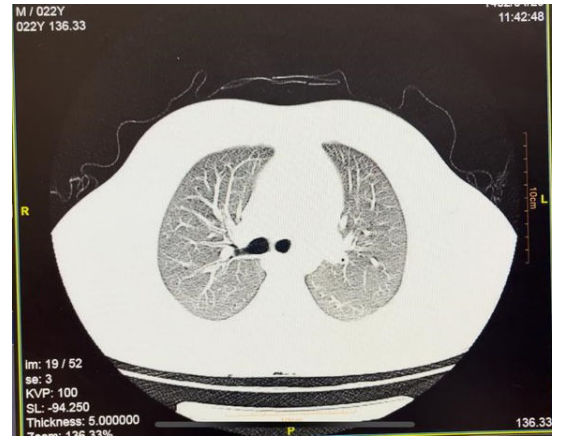

A follow-up lung CT scan on the day of discharge revealed clear lung parenchyma with no visible remnants of previous opacities. (Figure. 1-B)

Figure 1-B: Chest CT Scan After Treatment